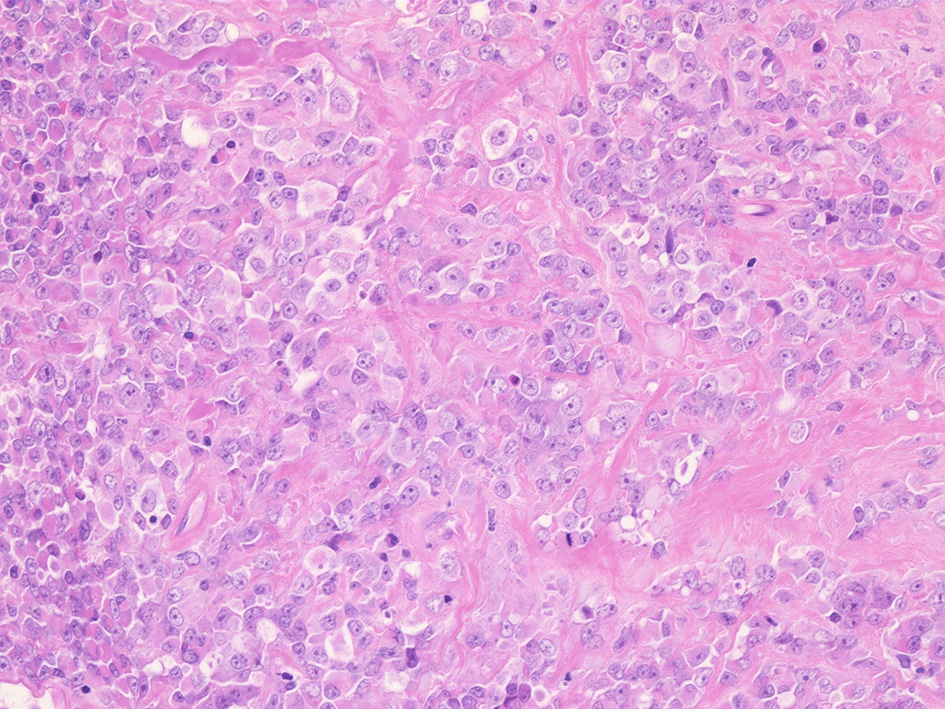

壁側胸膜腫瘤切除標本 病理組織所見

① rhabdoid cellsが密に増殖する組織像. 核は類円形vesicularで, 中心性の大型核小体を1個もつ. 細胞質は好酸性.

② 少量の線維性組織を間質に類円形/多稜形のvesicularな核と好酸性, 淡明な細胞質をもつ類上皮様の中~大型の細胞が集簇, 増殖している.mitosisが多い. 辺縁にはrhabdoid cellsのchohesiveな増殖が認められる.